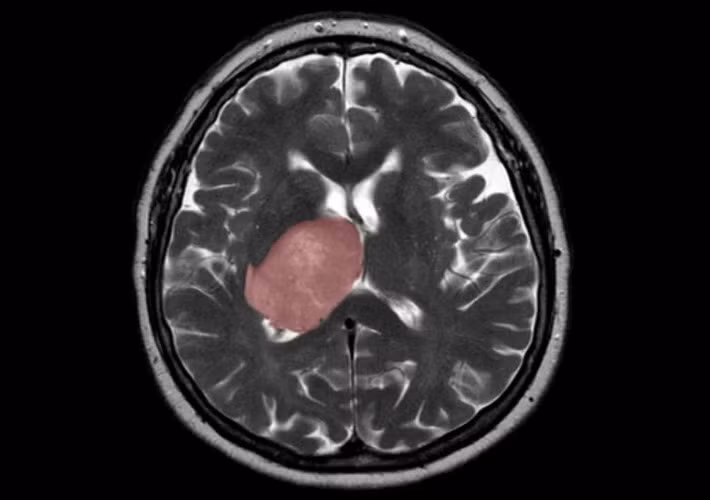

Khối u nguyên bào thần kinh đệm trong não.

Các nhà nghiên cứu đã áp dụng công nghệ máy học và giải trình tự RNA đơn bào mới nhất để lập bản đồ cấu tạo phân tử của tế bào gốc u nguyên bào thần kinh đệm (GSC). Họ đã tìm thấy các quần thể con GSC mới mang dấu hiệu phân tử của chứng viêm và kết hợp với các tế bào gốc ung thư khác bên trong khối u của bệnh nhân.

Nhóm nghiên cứu đã thu thập GSC từ 26 khối u của bệnh nhân, mở rộng trong phòng thí nghiệm để thu được đủ số lượng tế bào hiếm này và phân tích chúng. Gần 70.000 tế bào đã được phân tích bằng giải trình tự RNA đơn bào, giúp phát hiện những gen trong các tế bào riêng lẻ. Quá trình này đã được dẫn đầu bởi Laura Richards - một nghiên cứu sinh tại phòng thí nghiệm của Pugh.

Dữ liệu đã xác nhận tính không đồng nhất của bệnh trên diện rộng. Điều này có nghĩa là, mỗi khối u chứa nhiều tiểu quần thể tế bào gốc ung thư khác biệt về mặt phân tử. Chúng khiến khả năng tái phát rất cao, bởi liệu pháp hiện tại không thể xóa sổ tất cả các “dòng phụ” (khối u ác tính) khác nhau.